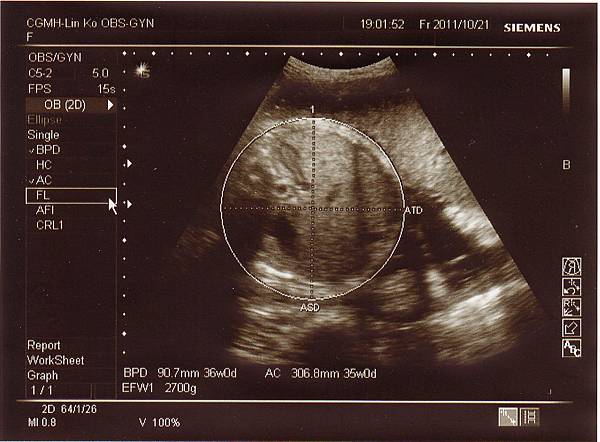

一開始產檢時,醫生量了頭圍結果約38週,也就是大了一周左右,

後來又換了角度量小了一些,但仍是正常範圍,

妹妹的體重來到2700多克,比上次多了一百克左右(還好有長大),